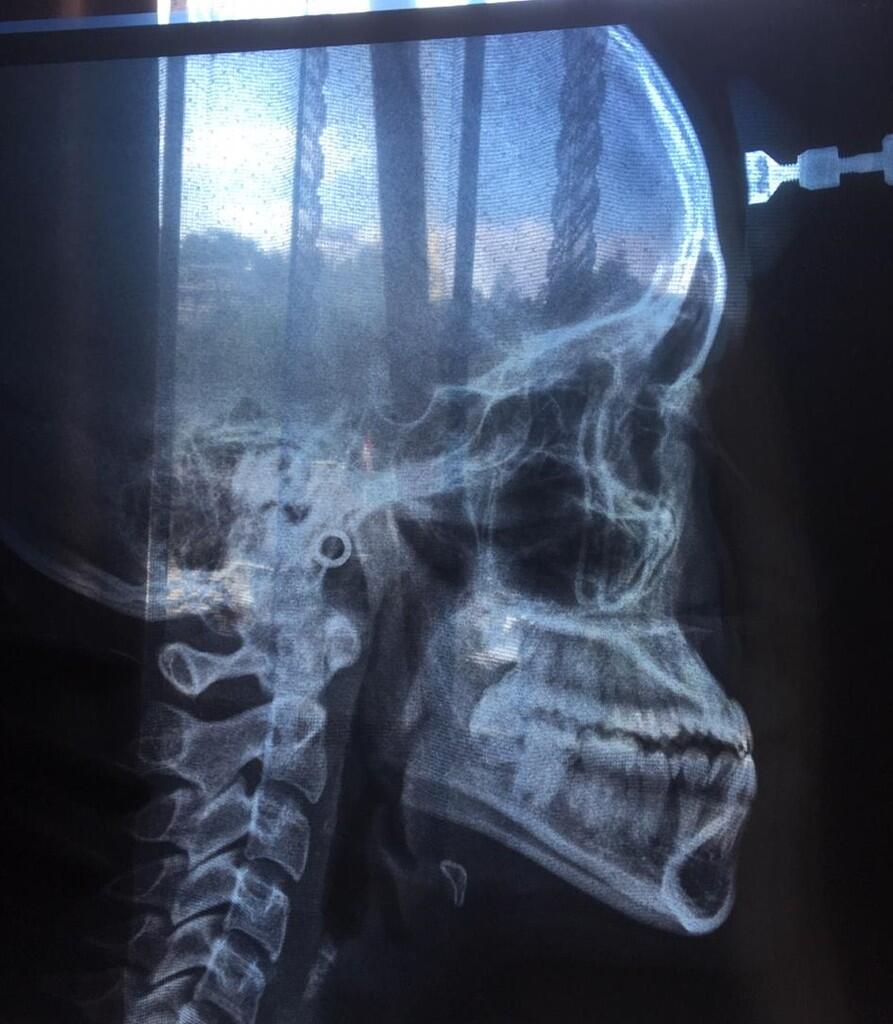

Halo gan, ane umur 20 dan sejak lama punya panggilan "si Cameuh" karena rahang bawah ane maju (foto diatas bukti Xray ane). Awalnya biasa aja tapi lama2 ane enek juga gan, akhirnya minggu lalu ane pergi ke klinik gigi terkemuka dengan niat awal mau pasang braces/behel. Sesampainya disana, oleh dokter gigi nya ane diperiksa dan menurut beliau gigi ane ini masuk ke Class 3, yang udah parah banget dan gak akan bisa dibetulkan dengan behel. Akhirnya kasus ane ini ditolak dan ane disarankan untuk ke spesialis orthodonti untuk bedah skeletal, baru setelah itu bisa dilanjut dengan behel.